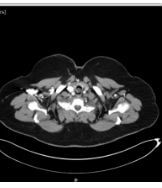

Contrast enhanced computed tomography (CECT) of neck and thorax reported intraluminal mildly enhancing polypoidal mass lesion measuring 2.58 x 1.54 x 1.51 cm (Cc X AP X Tr) in the upper trachea at the level of C6, C7 vertebral body. Significant luminal compromise was noted at the level of the mass lesion. Rest of the lung parenchyma was unremarkable. Flexible bronchoscopy examination revealed a large polyploidal growth approximately 3 cm from the vocal cords. The growth was moving with respiration and causing critical airway narrowing at the upper trachea (approximately 80%).

CECT at presentation: Intraluminal mass lesion in the upper trachea

CECT at presentation